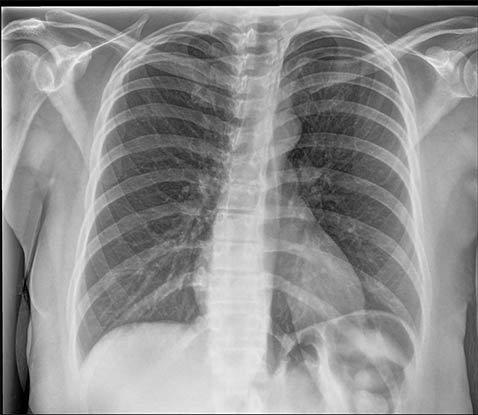

SmartGrid 处理的影像质量与使用防散射滤线栅采集的影像相当,但床边胸部影像方面患者剂量会减少。它会抑制散射的作用,从而改善解剖结构对比度。在不使用防散射滤线栅的情况下,滤线栅状影像质量的好处是加快工作流程并方便放射科技师成像。